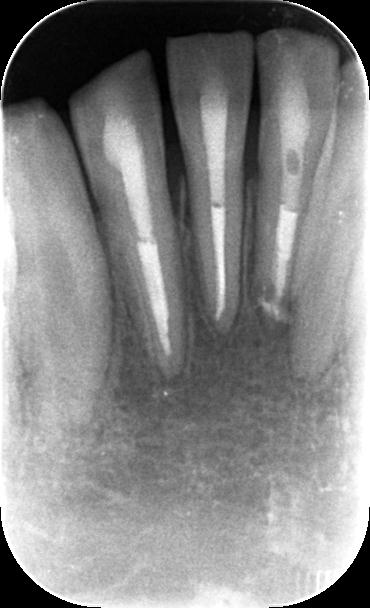

初診時のレントゲンです。右下1番、2番の根の先に透過像を認め(緑囲い部位)、前歯は激しく動揺している状態でした。しかしながらこの時点で歯髄電気診https://www.quint-j.co.jp/web/keyword/keyword.php?no=35698

冷温反応、打診などの検査を行ったところ歯の神経が生きている可能性を示唆する検査結果であったため経過観察といたしました。